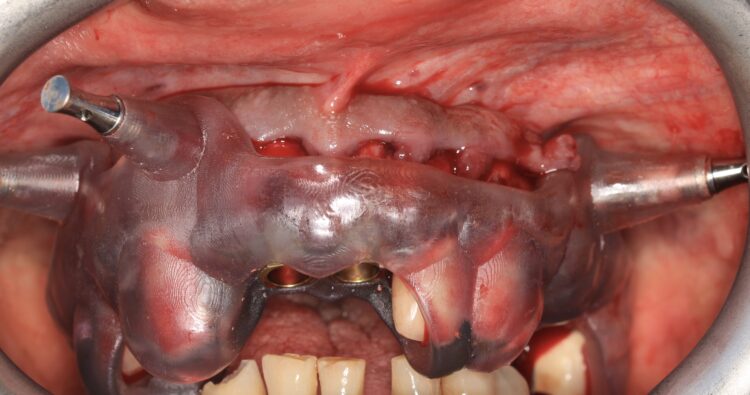

The design of the provisional prosthesis followed the Gallucci prosthetic guide protocol[i] providing a 3D printed composite bridge with palatal support. The palatal support sits below the fitting surface of the bridge and is only used to locate the bridge in centric occlusion using the hard palate of the patient. This bridge is an exact copy of the digital wax-up used to plan the implant positions. The use of guided surgery guarantees that the implants are placed precisely according to the plan.

The provisional restoration in this case had prefabricated prosthetic channels to match the same planned implant positions and angulations. This provisional was located in the mouth using the hard palate and attached on the titanium cylinders that penetrate through the bridge, with the use of a composite based light cured material.

The provisional prosthesis was then modified; the palatal part was removed and the bridge was relined with the use of a composite based flowable material, making sure that mechanically polished deep ovate pontics were designed for adequate sculpturing and adaptation of the soft tissue. A titanium wire 2mm in diameter was inserted into the bridge improving its rigidity and strength.